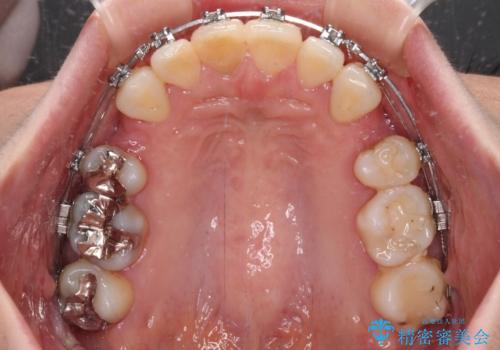

- 矯正装置

- メタルブラケット

- 八重歯と上の前歯が出っ歯になっていることを気にして来院された患者様です。

横から見た際の口元の飛び出した印象も改善したいとのことで、上下左右の第一小臼歯4本を抜歯し、ワイヤー装置にて抜歯矯正を行うこととしました。

前歯の変色している歯は、神経組織が壊死していたため、矯正治療前に根管治療を実施し、矯正治療後にオールセラミッククラウンにて補綴治療を行うこととしました。

順調に歯が動き、補綴治療も含め2年弱で治療を終えることができました。